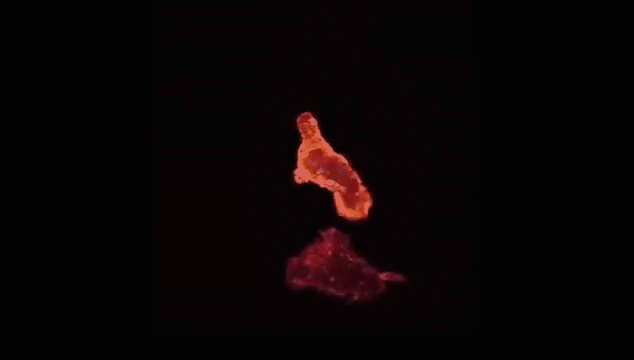

查明之后,T细胞(红)连接癌细胞(蓝),打破癌细胞外壁,向其表面引入毒性蛋白。